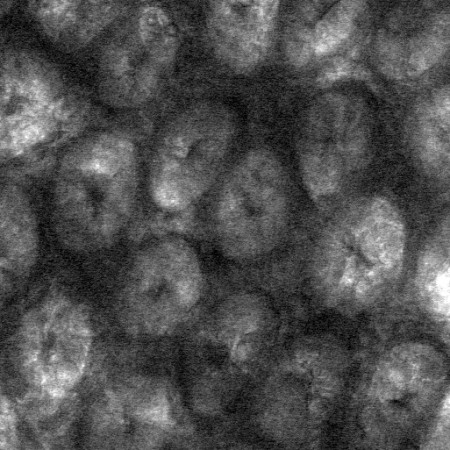

Image of the gut surface taken using brightfield microscopy. The circular features are collections of cells, called crypts, that make up the surface of the colon.